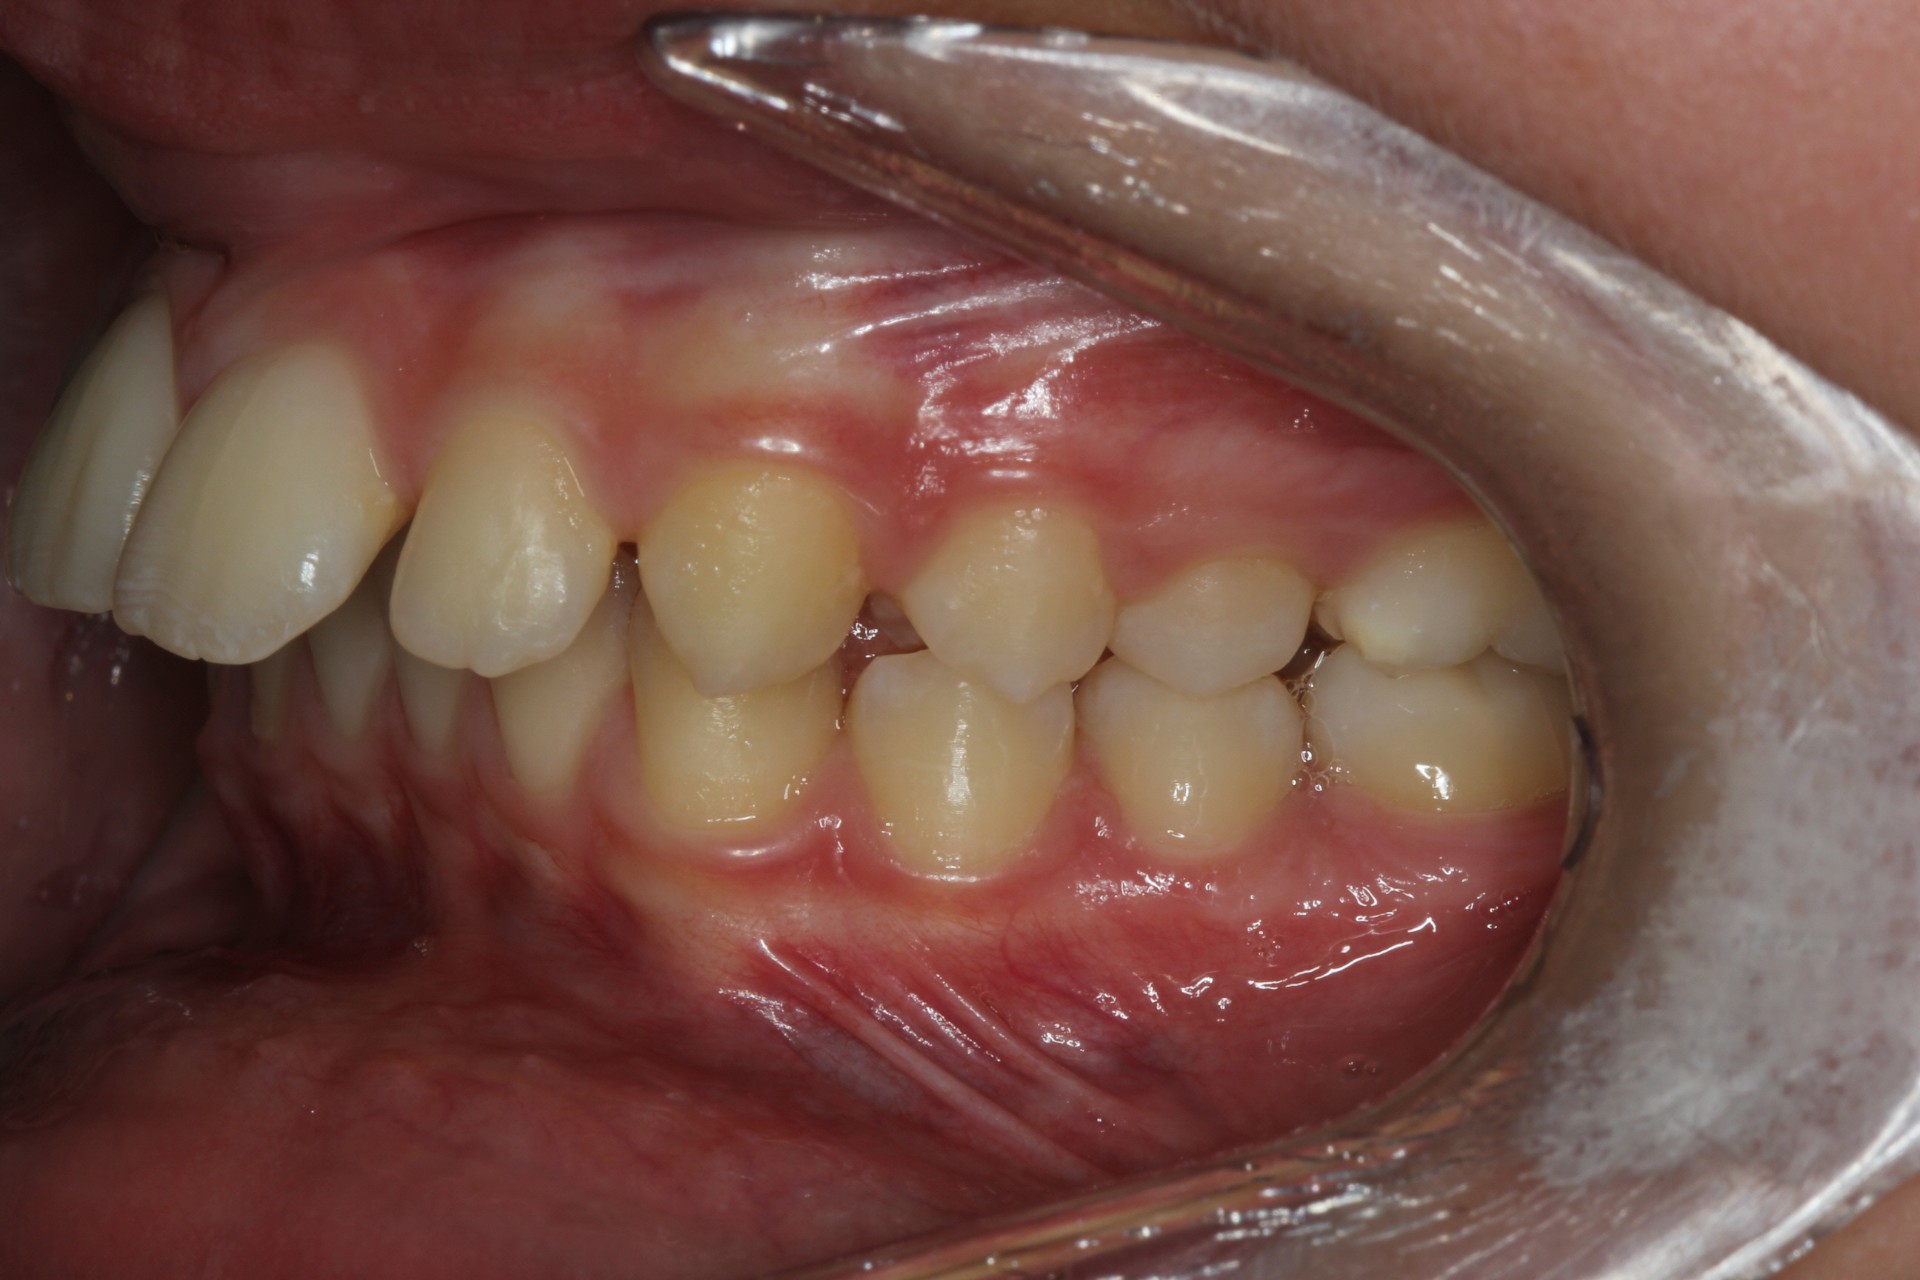

Protruding front teeth and spacing – Child case